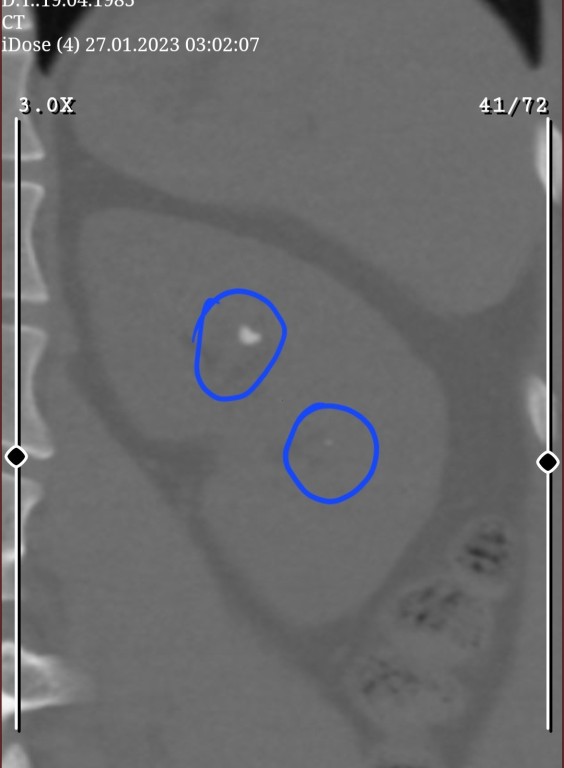

Sol böbrekte 8mm taş var önceki ay kırım yaptırdım 2 bölünmüş

bu ay sonu tekrardan kırım yaptıracağım suan vücudun ph yuksek tutup taşın yumumasını umuyoruz.

ara ara birşey çıkıyor ama görülmeyecek boyutta numune alıp kalsiyum mu üre mi

olduğunu öğrenemedik.